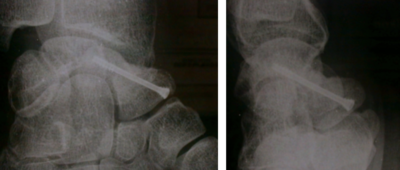

Stabilisation la fracture par vis ou broches

Le traitement des fractures déplacées est chirurgical. Il consiste à réduire le déplacement puis à stabiliser la fracture (par vis ou broches).